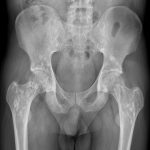

Loãng xương (Osteoporosis) là tình trạng giảm mật độ Canxi trong một đơn vị thể tích xương. Loãng xương là tình trạng bệnh lý phổ biến, có thể gây ra các hậu quả nặng nề cho cá nhân và xã hội. Tuổi gặp nhiều nhất ở phụ nữ sau mãn kinh, ngoài ra có thể gặp ở người trẻ tuổi hoặc thứ phát sau bệnh lý thận, cận giáp, bất động. Khi loãng xương, các bè xương mất dần dẫn tới cấu trúc xương yếu…